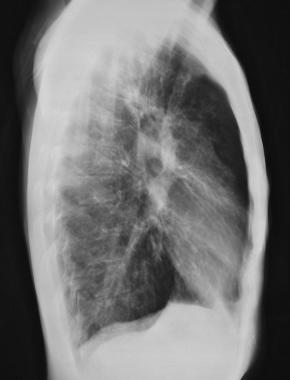

图1 患囊性纤维化的青年男性 , 显示过度充气和上叶支气管扩张 。

图2 侧位胸片显示胸骨后间隙增大(充气过多)